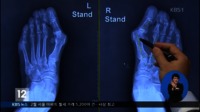

남성 무지외반증 환자 급증,키높이 깔창·구두 때문?

주로 여성에게 많이 발생하는 것으로 알려졌던 '무지외반증'이 남성에게도 일어나고 있어 주의가 요구되고 있다.'무지외반증'은 엄지발가락 관절을 기준으로 발가락의 뼈가 바깥쪽으로 튀어나오면서, 발 뒤꿈치 쪽 뼈는 안쪽으로 튀어나오는 변형을 말한다. 앞이 좁고 발 뒤꿈치를